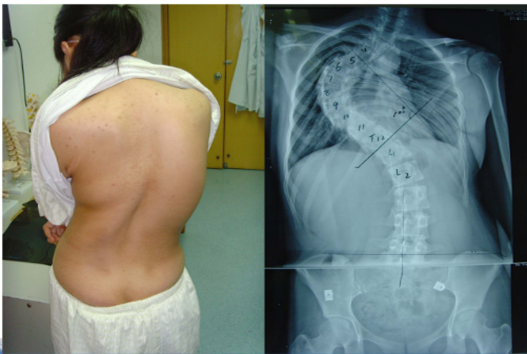

脊柱侧弯矫正

脊柱侧弯(AIS)指脊柱三维结构畸形,包括冠状位、矢状位和轴位的脊柱椎体排列异常,脊柱偏离正中位置,身体向一侧弯曲的骨骼畸形,包括特发性脊柱侧弯,先天性脊柱侧弯、神经肌肉型脊柱侧弯等。

案例一